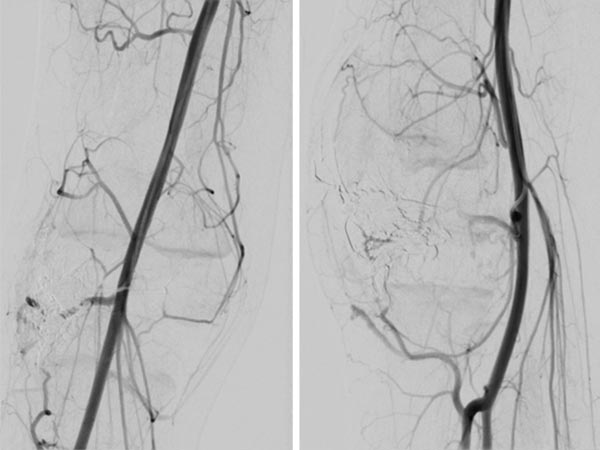

The repeat DSA 4 months after the previous embolization (left AP, right lateral) shows an early, circumscribed recurrence. Especially in the case of AVMs associated with a PTEN hamartoma syndrome, patients must attend for follow-up at short intervals, as these AVMs in particular have a high tendency to recur.